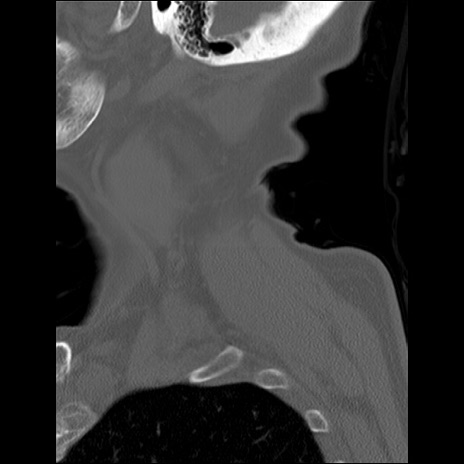

症例48 頚椎CT(矢状断像)

頚椎CT